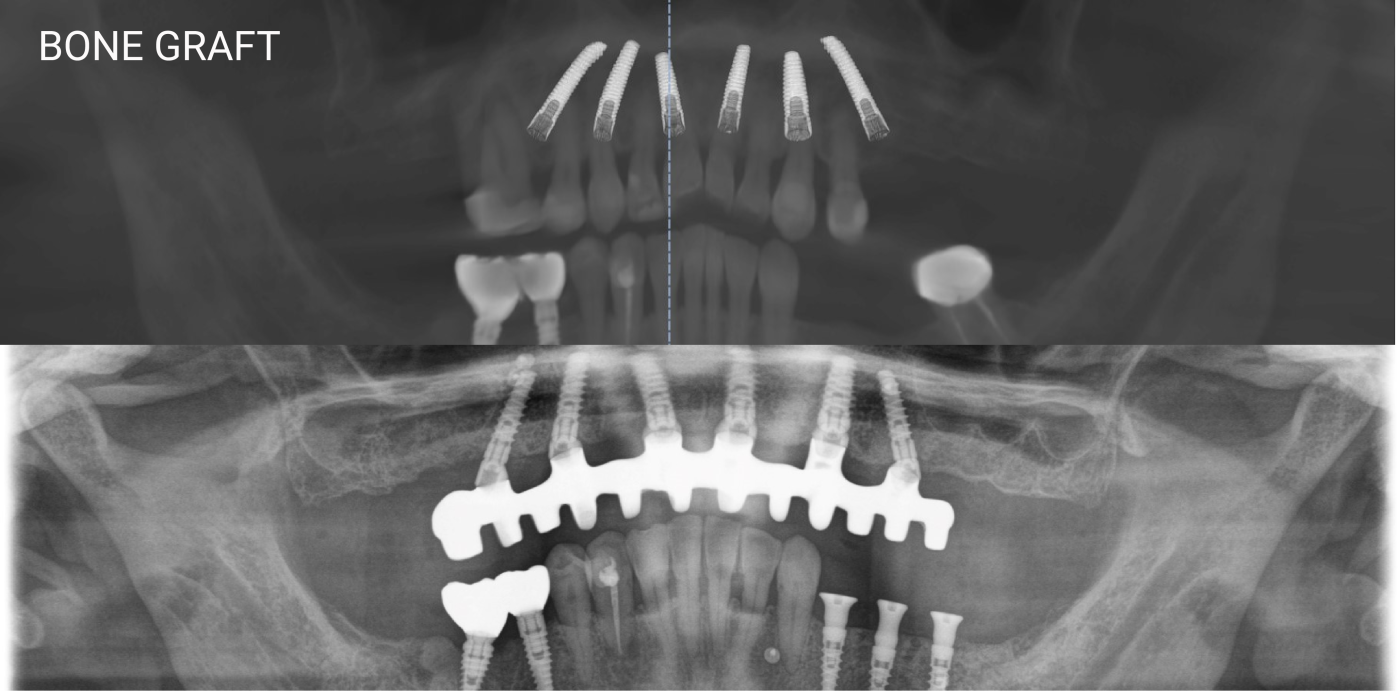

The latest Cone Beam CT Scanner: to assist our doctors in accurate diagnosis and coming up with treatment plan

Nobel Clinician software: to help our doctors determine the most suitable position for implant placement